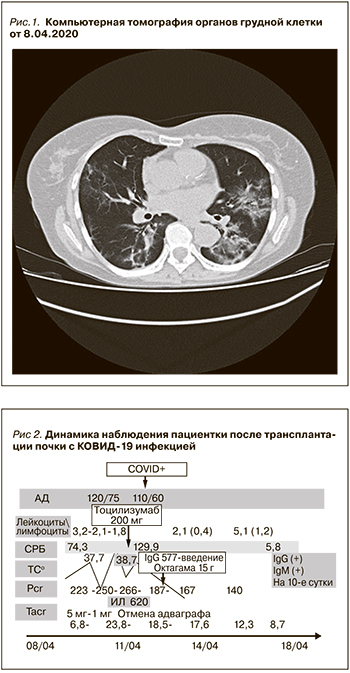

Пациентке была скорректирована иммуносупрессивная терапия: доза такролимуса пролонгированного действия с 5 мг в сутки снижена до 1,5 мг в сутки, метилпреднизолон был увеличен до 8 мг в сутки, отменен мофетила микофенолат и назначена следующая терапия: лопинавир 200 мг/ритонавир 50 мг 2 раза в сутки, гидроксихлорохин 400 мг в сутки, амоксициллин/сульбактам 4,5 г в сутки; антикоагулянтная терапия – далтепарин натрия 5000 ЕД в сутки. Динамика клинико-лабораторных данных представлена на рис. 2.

На фоне вышеуказанной терапии развилась дисфункция трансплантированной почки, сохранялась выраженная лихорадка, прогрессировала лейкопения/лимфопения, значительно выросла концентрация такролимуса в крови, несмотря на значительное снижение дозы такролимуса – более чем в 3 раза, наросла концентрация С-реактивного белка. Зарегистрирована отрицательная динамика при компьютерной томографии органов грудной клетки (рис. 3 и 4) Отмечено прогрессирующее снижение SpO2 c 97 до 86%, несмотря на высокопоточную оксигенотерапию, антибактериальную и антикоагулянтную терапию

Пациентке был отменен прием такролимуса до нормализации концентрации препарата в крови, несмотря на отмену лопинавира/ритонавира через 3 дня приема последнего. Проводился постоянный мониторинг концентраций такролимуса. Назначен тоцилизумаб в дозе 200 мг в сутки, затем в/в введение иммуноглобулинов G.